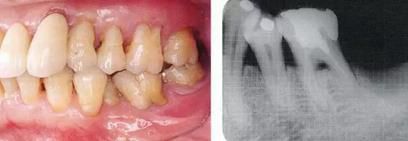

360截圖20170422101945505.jpg

▲圖9-1,2

▲圖9-1 預(yù)定進行正畸治療的患者,下頜磨牙區(qū)的右下6,7牙根接近,并在右下7遠(yuǎn)中存在垂直性骨組織缺損。對牙體狀況、牙周組織、咬合情況進行診斷后制定出的治療方案為:將右下6拔除,對右下7遠(yuǎn)中的骨組織缺失進行再生療法。

▲圖9-2 同部位X光片。右下6遠(yuǎn)中存在牙根接近,較深的骨組織缺損以及II度根分叉病變,所以將其拔除。

360截圖20170422101957225.jpg

▲圖9-3

拔牙后1周的狀態(tài)。愈合后,預(yù)定進行正畸治療穩(wěn)定牙列。